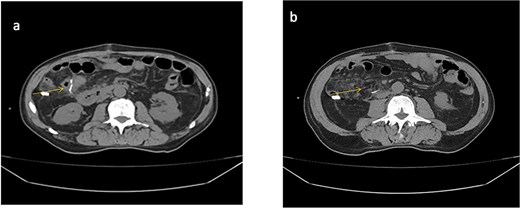

A follow-up abdominal CT scan revealed post-surgical changes consistent with a right hemicolectomy and ileotransverse anastomosis, along with a moderate amount of free intraperitoneal fluid (Fig. 2).

Abdominal CT scan (non-contrast). (a) Anastomotic staples and drain trajectory. (b) Presence of free intraperitoneal fluid.